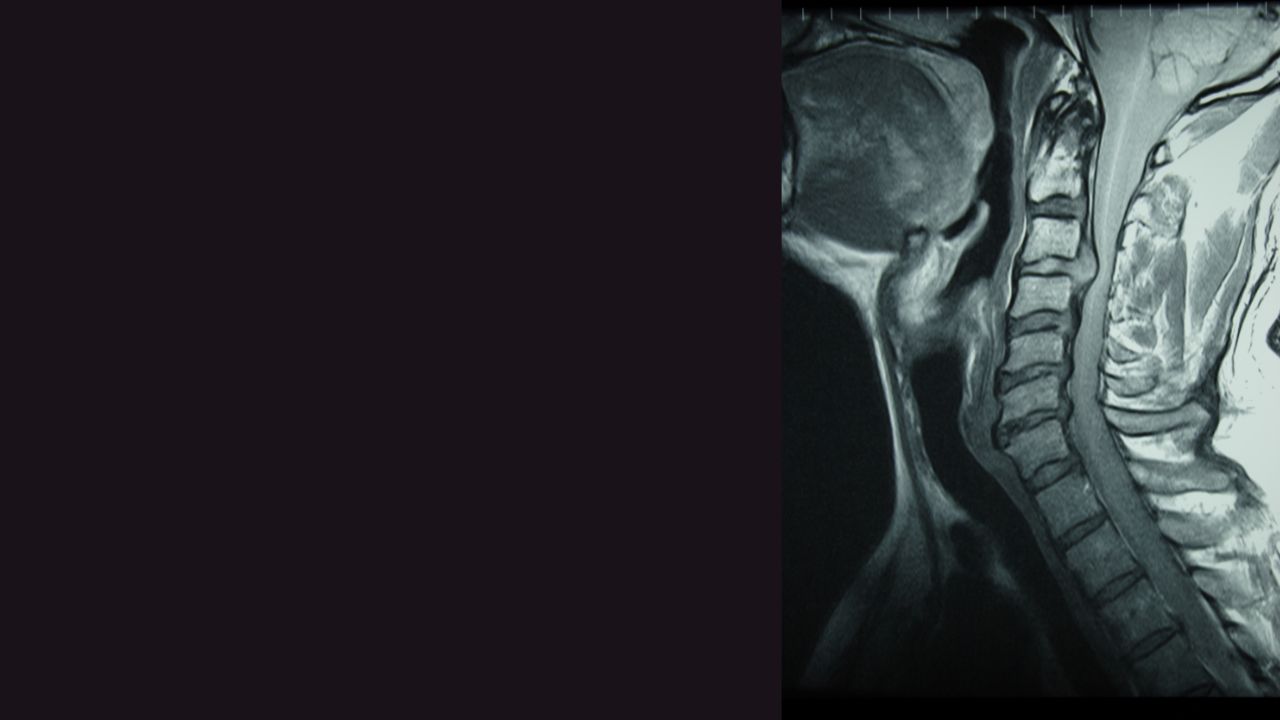

Before starting any treatment, chiropractors may conduct imaging tests such as X-rays, MRI, or CT scans to visualize the cervical spine and identify the extent of disc herniation. These images help guide the chiropractor in developing a personalized treatment plan and ensuring the safety of adjustments.

Before delving into cervical disc herniation, it's essential to understand the anatomy of the cervical spine. The cervical spine consists of seven vertebrae labeled C1 to C7, stacked on top of each other and separated by intervertebral discs. These discs act as shock absorbers, providing cushioning between the vertebrae and allowing for smooth movement of the neck.

Each intervertebral disc has two main components: the tough outer layer called the annulus fibrosus and the soft gel-like inner core called the nucleus pulposus. The annulus fibrosus helps stabilize the disc, while the nucleus pulposus absorbs pressure and allows for flexibility.